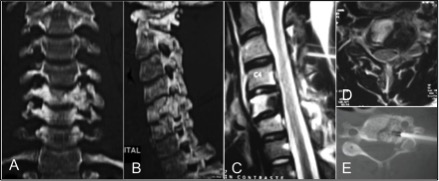

Osteosarcoma “tipo osteoblastoma” de columna cervical. A propósito de un caso. [Osteoblastoma like osteosarcoma of the cervical spine]